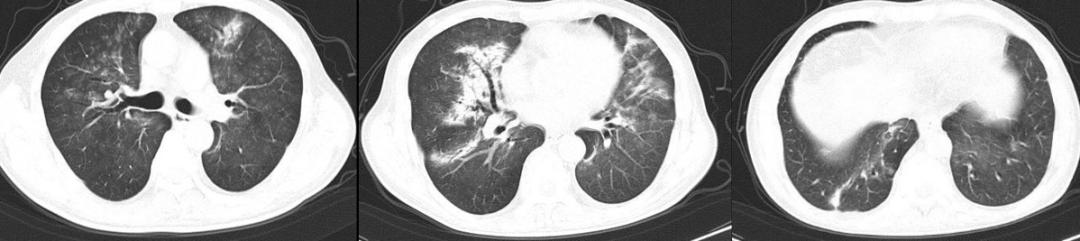

病例: 74岁女性咳嗽咳痰伴气短1月余,已经有亚急性过程了,1月前无明显诱因出现咳嗽,伴喘鸣音,白痰,不易咳出,活动后气短。当地抗感染治疗效果不佳。实验室检查:血常规 WBC 4.52*10^9/L,LY# 0.93*10^9/L,NE% 72.3%。虽然感染指标并不高,但两肺有多发病变。

胸部CT示(12-18):两肺多发斑片絮状影,右中肺及两下肺实变,考虑感染可能。

外院报告直接报告感染,患者经历了各种抗生素的挑战。我们收入院考虑的是急性呼吸衰竭、重症肺炎。在入院检验检查中发现患者血沉较快,其他微生物检查均为阴性:炎症指标:WBC 4.37*10^9/L,NE% 47.1%,ESR 55 mm/h,铁蛋白 107.40ng/mL,IL-6 2.34pg/mL,PCT: 0.1ng/mL,CRP 2.64mg/L。病原学检查:结核感染T细胞检测、CMV-DNA、ADV-DNA、EB-DNA、呼吸道感染病原体IgM抗体八联均无明显异常。痰液、肺泡灌洗液一般细菌及真菌培养、GM试验均未见明显异常。血G试验、GM试验无异常。血隐球菌荚膜抗原检测:阴性。

支气管镜检查:各段叶支气管通畅,黏膜正常,未见明显气管分泌物、新生物、溃疡、活动性出血;初始治疗方案:D1-D3:比阿培南 0.3g q6h+替加环素 100mg q12h+甲强龙 40mg qd。

治疗中患者的氧合指数仍然在快速下降,我们复查CT,显示大部分病变在进展。

图:胸部CT(12-24):两肺纹理增多,两肺门影增浓,两肺野内多发斑片影,较前2021-12-18部分稍有好转,部分稍明显。

仔细比对后,我发现有一个病灶吸收了,机化性肺炎?气管镜下并没有明显感染的征象,后来,NGS只检出纹带棒状杆菌7个序列、光滑念珠菌16个序列,载量很低,而且这两个病原体本身就存在于呼吸道,所以我将它们定义为阴性。

这时进行治疗调整:2021.12.24-12.26:比阿培南0.3g q6h+替加环素 100mg q12h+甲强龙 120mg qd;12.27-2022.01.02:哌拉西林他唑巴坦4.5g q6h+甲强龙 40 mg qd。激素加量、抗生素两天后减量了。治疗效果体现在氧合指数上,患者的氧合指数开始抬头。经过7天的治疗,CT显示所有病灶都在吸收。

图:胸部CT(12-31):两肺野内多发斑片影,较前好转。

修正诊断患者为机化性肺炎,携带激素出院。只要缓慢减量、疗程足够长,大部分患者不会反弹